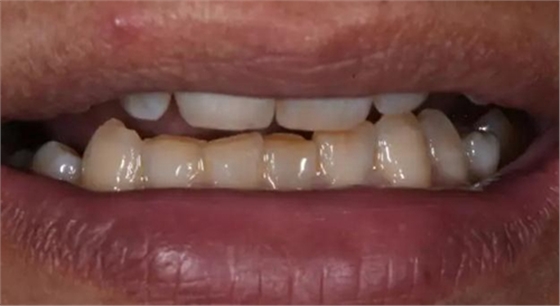

術后口內(nèi)照片

修復體戴入口內(nèi)后照片,與鄰牙鄰接良好。